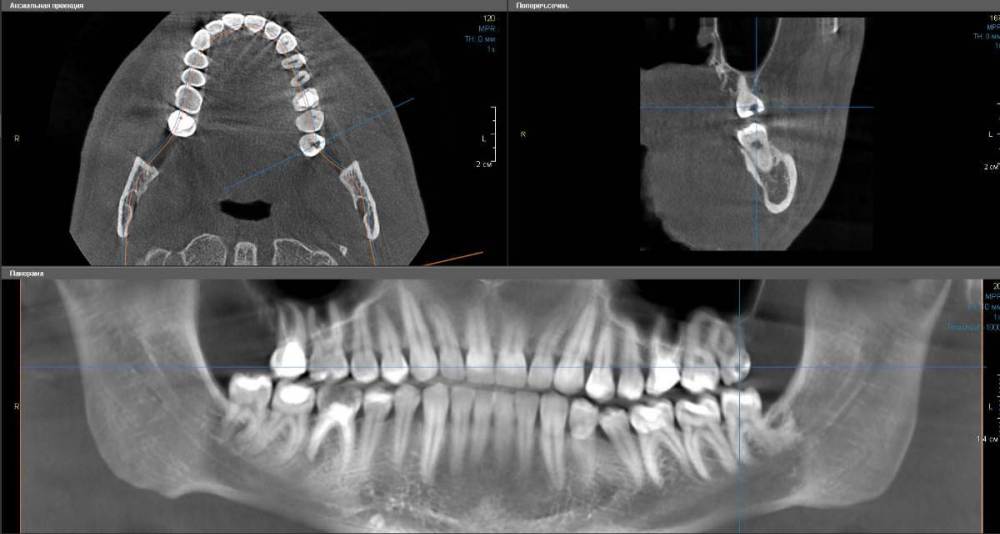

Первый зуб:

Левая верхняя восьмерка (28), был обнаружен кариес, пролечен пару недель назад, запломбирован. На КТ виднеется достаточно объемная полость. Что бы это могло быть?  Кариозная полость, упущенная врачом? Не могло ли быть такого, что материал при пломбировке заполнил собой не всю ранее подготовленную врачом полость? (см. первый скриншот)

tooth1.jpg